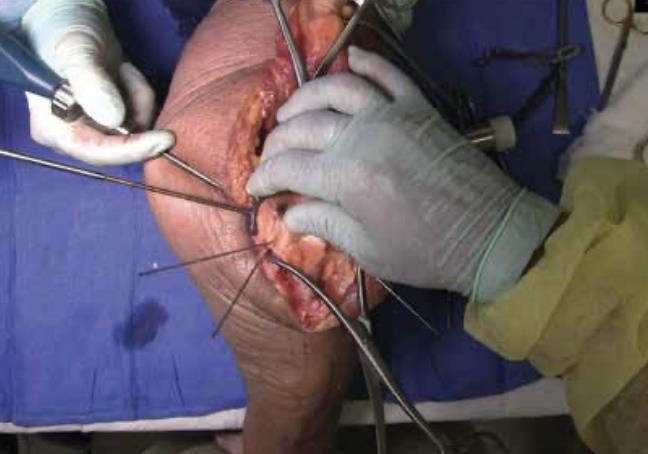

• Fracture exposure

• Reflect the olecranon and triceps proximally, exposing the fracture.

• Reduction

• Articular fragment

• Debride the fracture sites and reduce articular fragments.

• Column

• Reduce the articular portion to the humeral shaft using 1.5mm K-Wires.

• The K-Wire in each column should be placed as posterior and close to the midline as possible to prevent interference during Trochlea Compression Screw insertion.

• Release soft tissue from the tip of the medial and lateral epicondyles, and any osteophytes present, to expose for plate application.